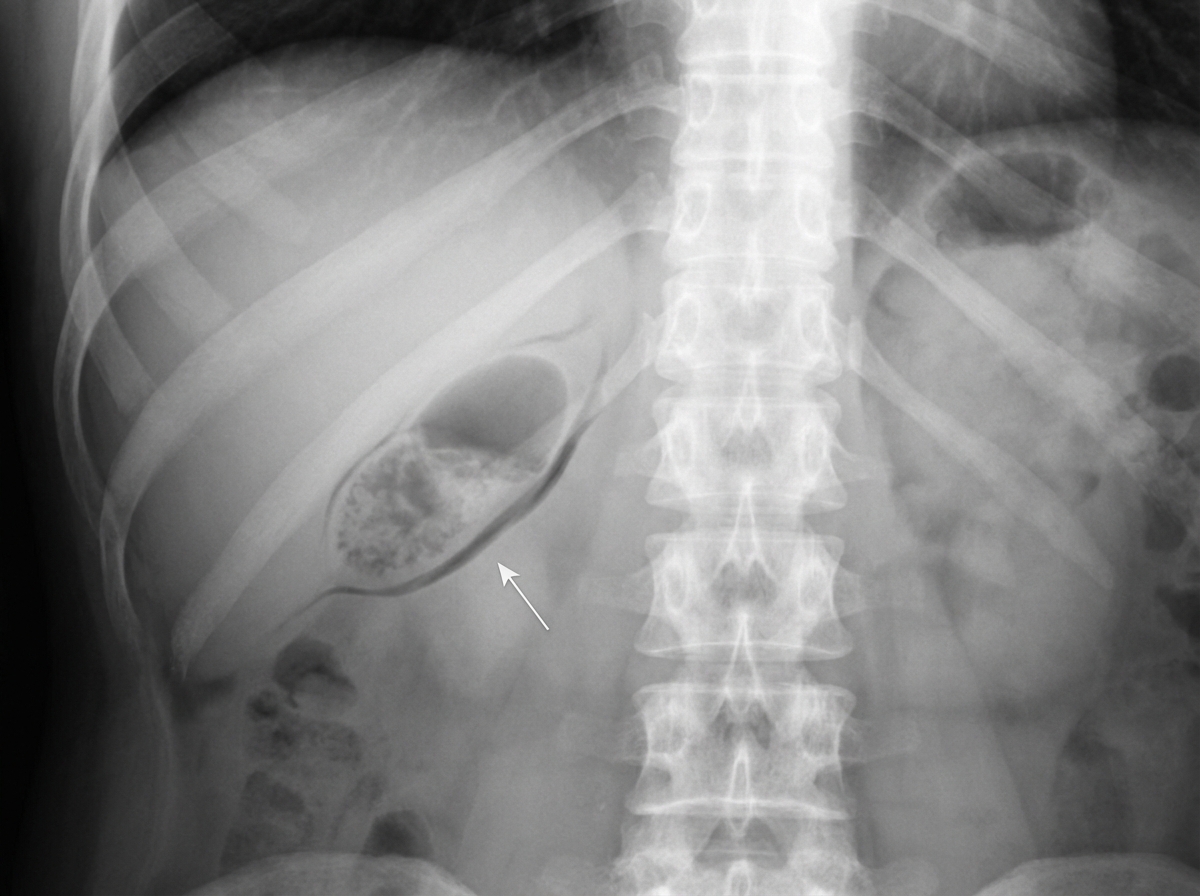

Explanation: **Explanation:** **Limey Bile (Milk of Calcium Bile)** is a rare condition where the gallbladder lumen is filled with a thick, semi-solid, radiopaque paste consisting primarily of **calcium carbonate**. 1. **Why Option C is Correct:** The characteristic consistency of limey bile is described as a **"toothpaste-like" emulsion**. It occurs due to chronic cholecystitis associated with a long-standing obstruction of the cystic duct. The stasis leads to the precipitation of calcium salts (carbonate, phosphate, or bilirubinate) within the gallbladder. 2. **Why Other Options are Incorrect:** * **Option A:** Limey bile is almost exclusively found in the **gallbladder**. It rarely enters the common bile duct (CBD) because the condition is usually predicated on a blocked cystic duct. * **Option B:** It is the opposite of thin and clear; it is thick, viscous, and opaque. * **Option D:** While it occurs in the setting of chronic inflammation, limey bile itself is not primarily characterized by bacterial concentration, but rather by its **high mineral/calcium content**. **High-Yield Clinical Pearls for NEET-PG:** * **Radiology:** It is one of the few conditions where the gallbladder can be visualized on a **plain X-ray (KUB)** without contrast, appearing as a diffuse opacification in the right upper quadrant. * **Pathogenesis:** Requires a combination of cystic duct obstruction and chronic low-grade inflammation. * **Management:** The treatment of choice is **cholecystectomy** (usually laparoscopic), as it is associated with chronic cholecystitis and potential complications. * **Differential Diagnosis:** Must be distinguished from a "Porcelain Gallbladder" (where calcium is in the *wall*) and "Biliary Sludge" (which is not typically radiopaque on X-ray).